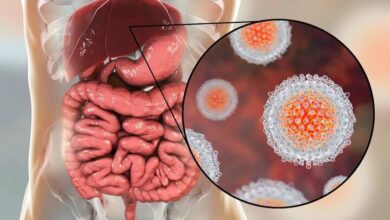

تجربه موفق واکسیناسیون سرخک ؛ یک مدل موفق برای از بین بردن هپاتیت C در کشور – آژانس خبری مهر | اخبار ایرانی و جهانی

مینو محور ، متخصص بیماریهای عفونی و اعضای هیئت علمی دانشگاه علوم پزشکی تهران ، به اهمیت بیماری هپاتیت C…

آمار هپاتیت در ایران اعلام شد

به گفته وزارت بهداشت و آموزش پزشکی ، رئیس وزارت بهداشت و آموزش پزشکی در روز بین المللی وزارت بهداشت…